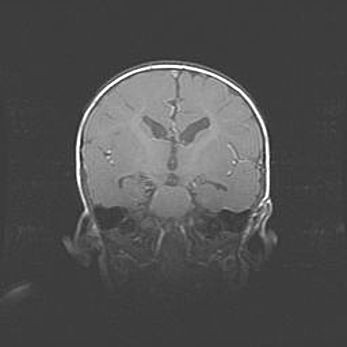

Мальформация Денди-Уокера. Киста задней черепной ямки.

Агенезия мозолистого тела.

Возраст: 2,5 месяца

Вес: 2420 г

Пол: женский

Окружность головы: 37 см

Срок гестации: 32 недели

Мальформация Денди—Уокера — редкий вид патологии ЦНС, представляющий собой врожденный порок развития каудального отдела ствола и червя мозжечка, ведущий к неполному раскрытию срединной (Мажанди) и латеральных (Лушка) апертур IV желудочка мозга. Для этогно синдрома характерна триада симптомов: гипотрофия червя мозжечка и/или полушарий мозжечка, кисты задней черепной ямки, гидроцефалия различной степени. В 70% случаев порок сочетается и с другими аномалиями головного мозга, в частности с агенезией мозолистого тела.